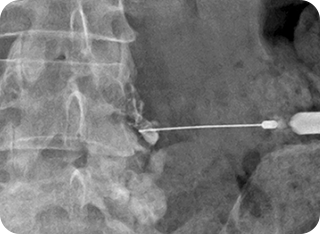

2

신경성형술(PEN)

가느다란 특수 카테터를 삽입해 유착된 신경을 풀어주고 약물을 주입하는 방식입니다.

절개 없이 진행되며, 만성 통증 환자에게 효과적입니다.

• #척추·관절 고주파 열치료

• #수핵성형술

• #섬유륜성형술

풍선확장술 사진1

풍선확장술 사진2

3

풍선확장술

미세한 풍선을 신경관이나 협착 부위에 삽입해 좁아진 공간을 확장시킨 뒤

약물을 투여합니다. 신경 압박을 줄이고 혈류를 개선하여 통증 완화와

기능 회복에 도움을 줍니다.